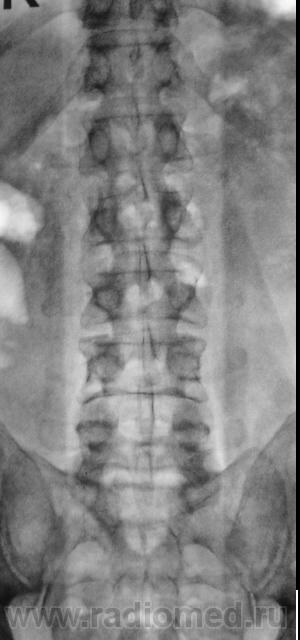

Пациент направлен на рентгенографию поясничного отдела позвоночника.

Надо доснять Л5-С1.

А может то уже S1-S2?

а симптом" рыбьего хвоста " есть или нет?...просто вопрос...

Специалисты, прокомментируйте, что есть на КТ, кроме остеохондроза.